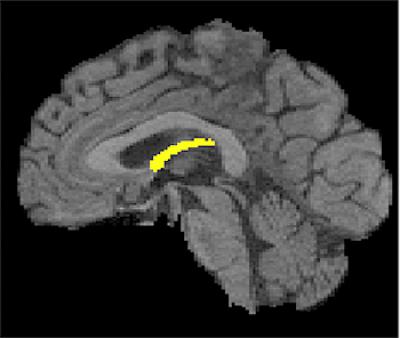

(SACRAMENTO, Calif.) — The degeneration of a small, wishbone-shaped structure deep inside the brain may provide the earliest clues to future cognitive decline, long before healthy older people exhibit clinical symptoms of memory loss or dementia, a study by researchers with the UC Davis Alzheimer's Disease Center has found.

The longitudinal study found that the only discernible brain differences between normal people who later developed cognitive impairment and those who did not were changes in their fornix, an organ that carries messages to and from the hippocampus, and that has long been known to play a role in memory.

Hippocampal atrophy occurs in the later stages of cognitive decline and is one of the most studied changes associated with the Alzheimer's disease process. However, changes to the fornix and other regions of the brain structurally connected to the hippocampus have not been as closely examined. The study found that degeneration of the fornix in relation to cognition was detectable even earlier than changes in the hippocampus.

"Although hippocampal measures have been studied much more deeply in relation to cognitive decline, our direct comparison between fornix and hippocampus measures suggests that fornix properties have a superior ability to identify incipient cognitive decline among healthy individuals," Fletcher said.